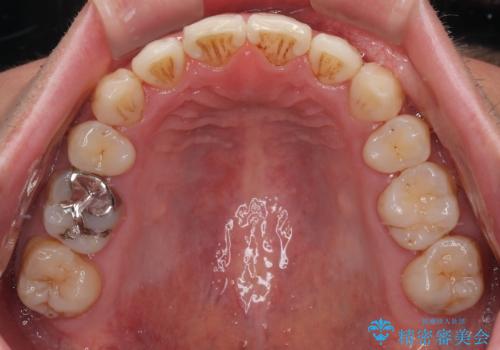

- 口元の突出感が強く、口が閉じにくいことを主訴として来院された患者さんの症例をご紹介します。

前歯部の叢生(デコボコ)も認められ、歯がきれいに並ぶためのスペースが不足している状態でした。

これらの問題を総合的に改善するため、上下左右の第一小臼歯を計4本抜歯し、スペースを確保する治療計画を立てました。